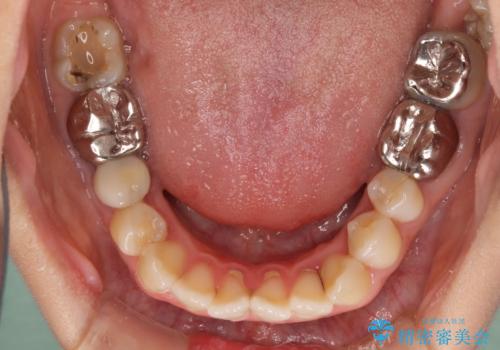

開咬と前突を改善 ワイヤー装置での抜歯矯正

- 口元の突出感と開咬を気にして来院された患者様です。

口元の突出感を改善するため、第一小臼歯を抜歯して口元を引っ込めることとしました。

一般的には上下左右の第一小臼歯4本を抜歯しますが、下顎に対して上顎が前方に位置しているため、まずは上顎小臼歯2本を抜歯し、治療経過を見て下顎小臼歯を抜歯するかどうかを決めていくこととしました。

元々むし歯の処置歯が多く、神経を取り除いている歯が多くありましたが、どうやら右上の前歯と小臼歯は外傷により神経を失った可能性があり、抜歯したスペース前後の歯が全く動かない状態でした。

結果として下顎の小臼歯は抜歯せず、右上の抜歯スペースはむし歯処置を兼ねてオールセラミックブリッジにて補綴治療を行うこととしました。

動かない歯での停滞や、出産と子育てなどにより治療期間は長期化しましたが、整った歯列にて仕上げることができました。